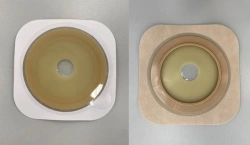

Medical product is intended for use in colostomies, ileostomies and urostomies for hermetic and secure attachment of stoma bags to the skin of the anterior abdominal wall, as well as to protect the skin of the peristomal area from stoma secretions and preserve the physiological functions of the skin due to the absorption of natural skin moisture (sweat, sebum).